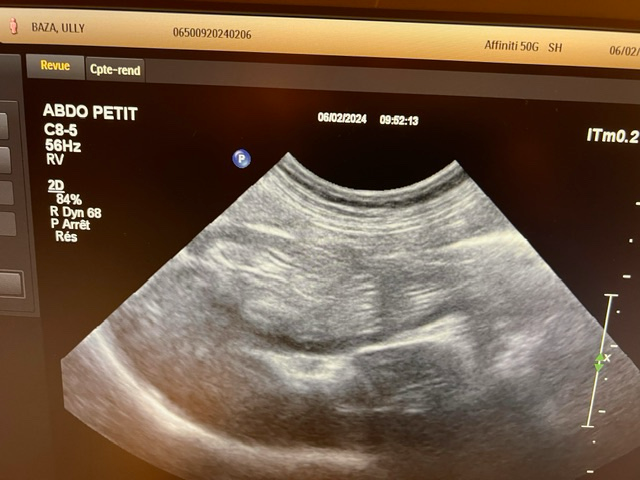

강아지가 목줄을 하고 산책 중에 갑자기 집에 가려고 차도로 뛰어드는바람에 교통사고가 났습니다. 천천히 달려오는 차에 부딪히기는 했지만 걱정돼서 바로 병원으로 갔고 엑스레이, 초음파, 혈액검사 다 시행했지만 이상이 없다고 얘기했습니다. 그런데 사고 이후로 계속 토를 해서 병원에 가서 구토약이랑 진통제를 받아와서 먹였는데도 계속 구토를 하네요ㅠ 사료를 그대로 토하는데 이게 스트레스때문인지 아니면 검사상에 이상이 있는지 여쭤보고 싶어서 글 남깁니다. 또한 가슴쪽을 부딪혔는데 흉부 엑스레이 상에서 이상소견이 있는지 확인 좀 부탁드립니다.

초음파 검사의 경우 초음파를 직접 본 사람이 아니면 찍어놓은 사진으로는 아무런 판단을 할 수 없고 해서도 안됩니다.

주치의의 판단이 가장 정확한 판단이겠으나 지현형으로 장기 손상이 일어나는 경우가 종종 있기 때문에 증상이 지속된다면 복부 초음파 검사를 다시 받아볼 필요가 있어 보입니다.